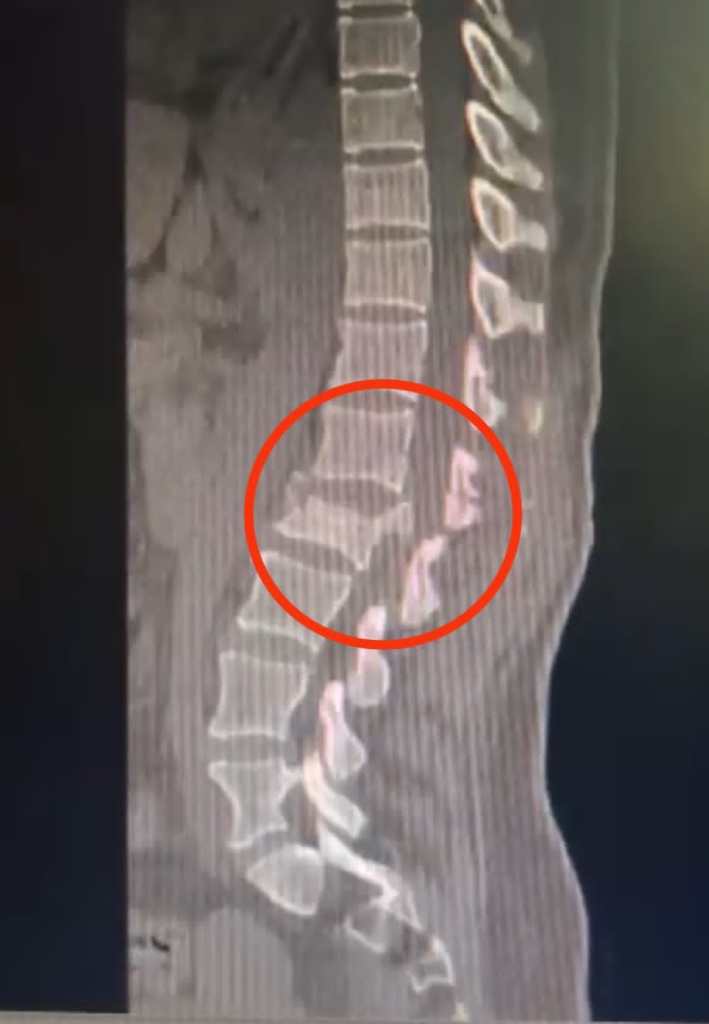

El jefe del servicio de neurocirugía de dicho nosocomio, Dr. Yuri Valdivieso Villena, indicó que la paciente llegó con contusiones múltiples e inmovilidad en ambas piernas. De manera inmediata se le realizó diversos exámenes que evidenció una fractura compleja en la segunda vértebra lumbar con un fragmento de hueso, que ingresó al canal medular con compromiso de los nervios y en los miembros inferiores de su cuerpo.